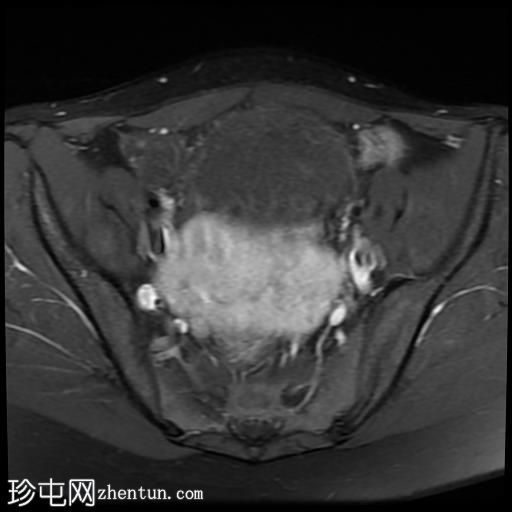

轴位T1加权像

增强脂肪抑制像

其中一个位于子宫上方,T2加权像呈中等信号,中心区域呈高信号,增强T1脂肪抑制像未见强化。右侧卵巢增大,增厚的血管蒂扭曲,未见强化,轴位和矢状位T2加权像均显示清晰。

另一个位于子宫后窝,T2加权像呈中等信号,增强扫描显示明显强化。

2个月前进行的MRI检查显示双侧卵巢肿块均有强化,右侧卵巢肿块未见扭转。